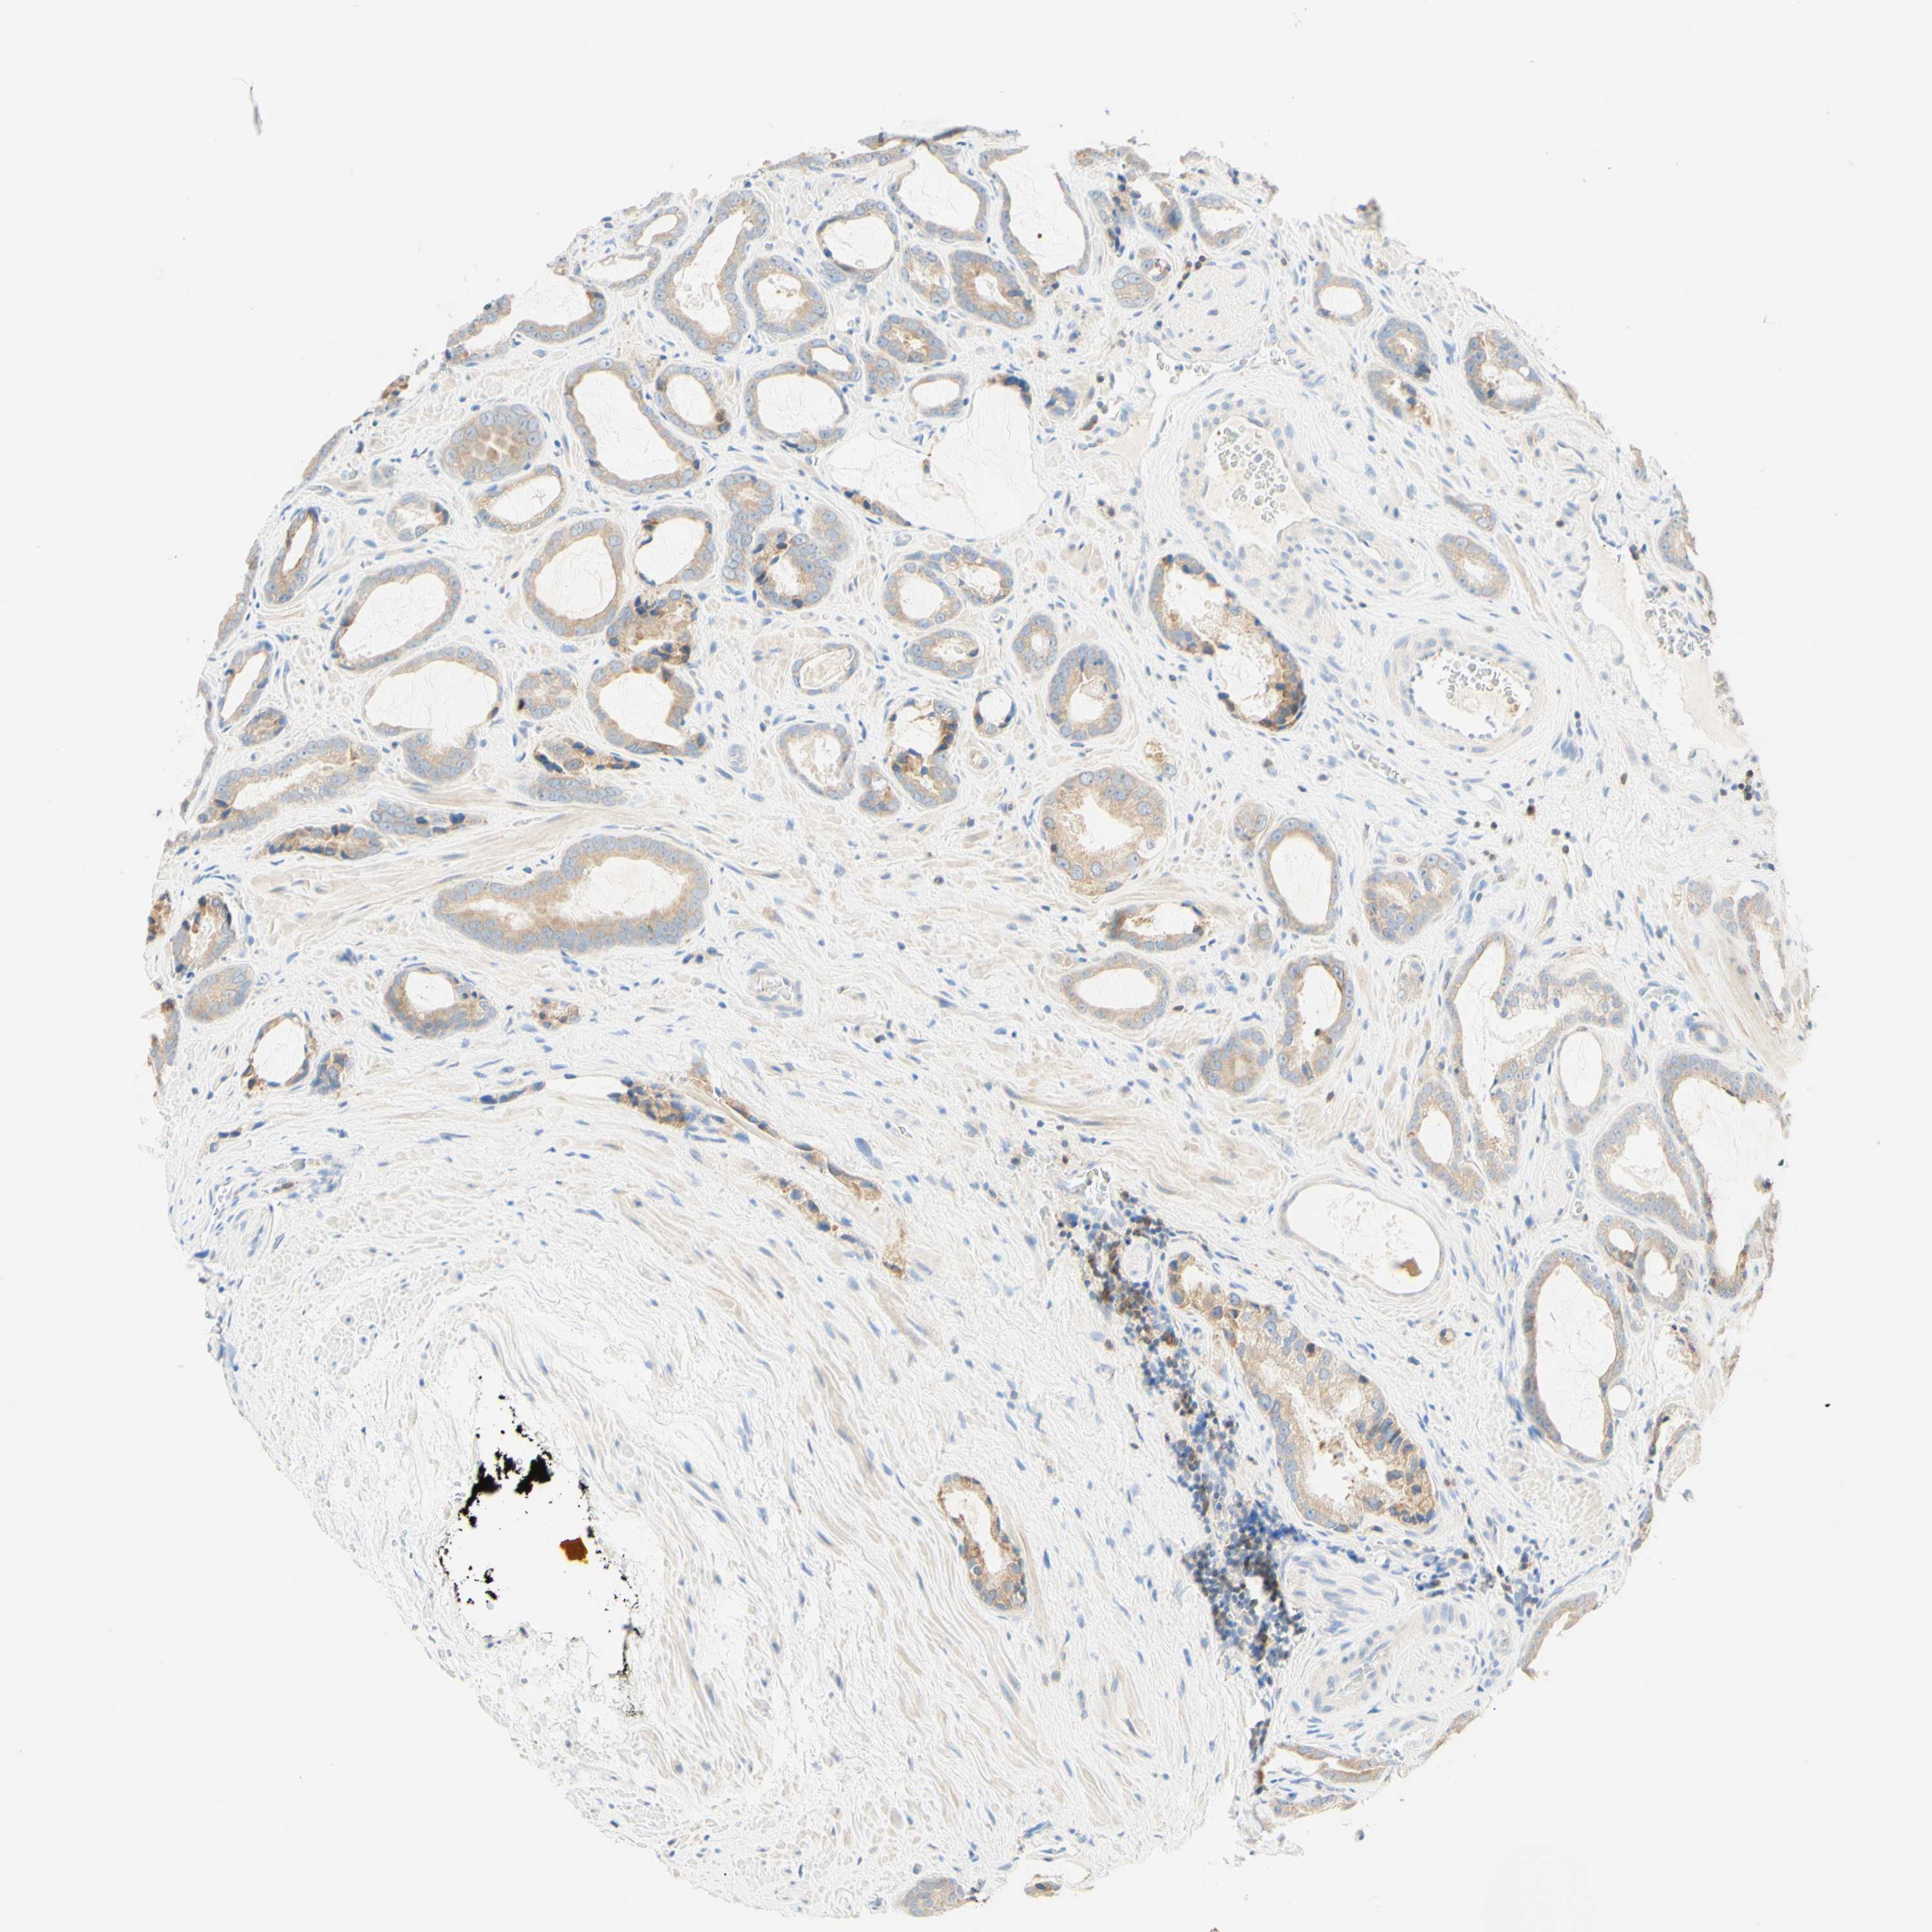

PROSTATE CANCER - Protein expressioni

A mouse-over function shows sample information and annotation data. Click on an image to view it in a full screen mode. Samples can be filtered based on level of antibody staining by selecting one or several of the following categories: high, medium, low and not detected. The assay and annotation is described here.

Antibody stainingi

Antibody staining in the annotated cell types in the current human tissue is reported as not detected, low, medium, or high, based on conventional immunohistochemistry profiling in selected tissues. This score is based on the combination of the staining intensity and fraction of stained cells.

Each image is clickable and will lead to virtual microscopy that enables deeper exploration of all samples and also displays staining intensity scores, fraction scores and subcellular localization as well as patient and tissue information for each sample.

Antibody HPA011157

Antibody CAB002223

Antibody CAB012978

Antibody CAB079960

Staining

High

Medium

Low

Not detected

Intensity

Strong

Moderate

Weak

Negative

Quantity

>75%

75%-25%

<25%

None

Location

Nuclear

Cytoplasmic/membranous

Cytoplasmic/membranous,nuclear

Adenocarcinoma, Low grade

Adenocarcinoma, High grade

Adenocarcinoma, Medium grade

Adenocarcinoma, NOS